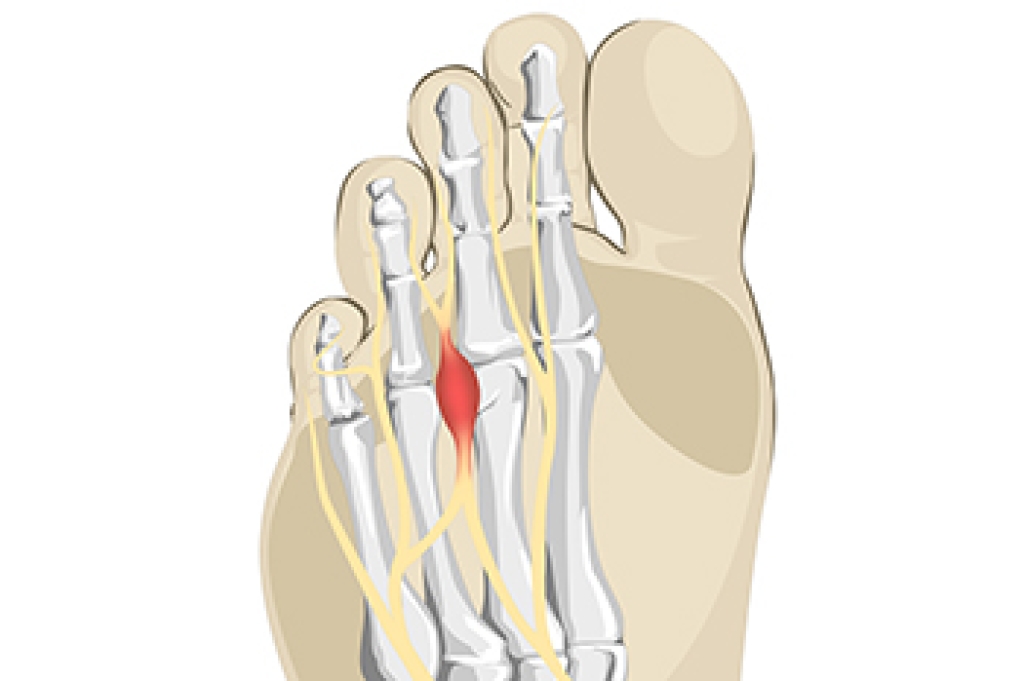

Morton's neuroma is a painful condition affecting the ball of the foot, typically between the third and fourth toes. It is not a true neuroma but can be debilitating, causing numbness, burning, or tingling. The condition often develops due to chronic trauma from repetitive pressure or activity, entrapment of the nerve between the metatarsal bones, inflammation of the intermetatarsal bursa that cushions the area, or damage from reduced blood flow. Chronic trauma refers to repeated stress that irritates the nerve, entrapment occurs when the nerve is compressed, bursitis causes swelling and irritation, and poor blood flow limits oxygen supply to the tissues. A podiatrist can diagnose the condition, recommend orthotics, footwear modifications, injections, or surgical options, if necessary. If you have pain in this part of your foot, it is suggested that you schedule an appointment with a podiatrist for an expert evaluation and effective relief solutions for what may be going on.

Morton's neuroma is a painful foot condition that commonly affects the areas between the second and third or third and fourth toe, although other areas of the foot are also susceptible. Morton’s neuroma is caused by an inflamed nerve in the foot that is being squeezed and aggravated by surrounding bones.